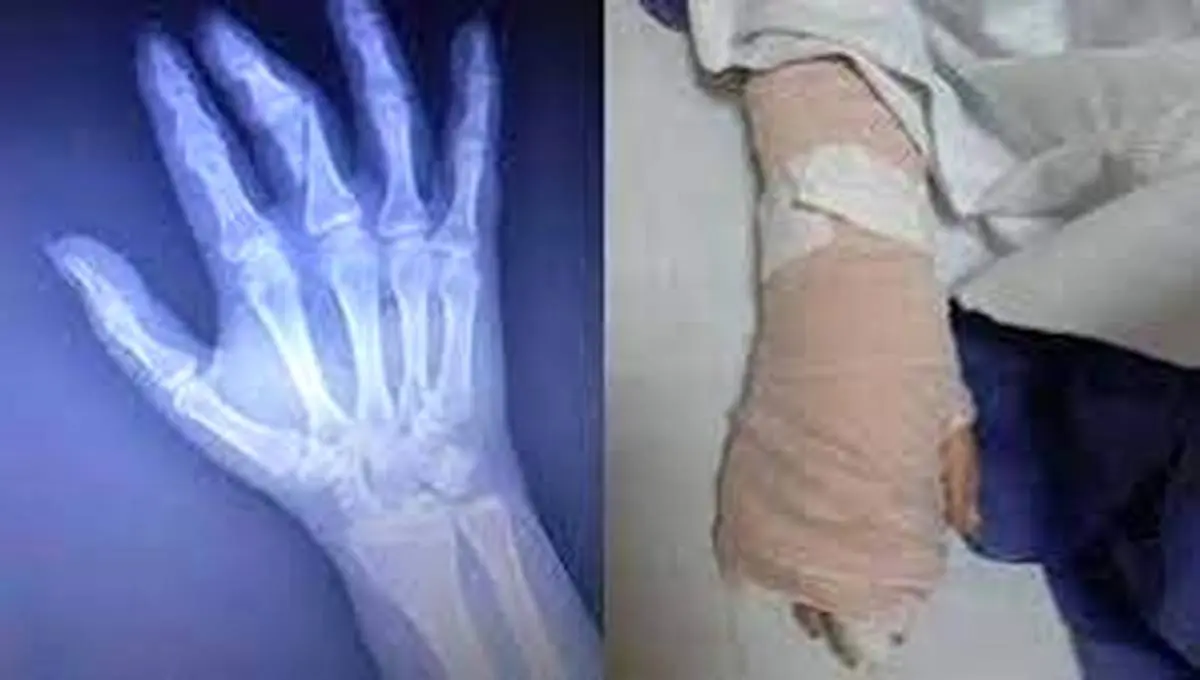

داستان از این قرار بود که فائزه مومنی، خبرنگار، در تاریخ ۲۷ اردیبهشتماه همزمان با روز جهانی ارتباطات برای تهیه گزارش از روند واکسیناسیون به یکی از مجموعه های اقماری یکی از دانشگاه های کشور میرود و بعد از انجام مصاحبه، به هنگام خروج با برخورد توهینآمیز مامور حراست مجموعه مواجه میشود. این مامور که تلاش میکند فایلهای مصاحبه خبرنگار را پاک کند، گویا بعد از مشاهده اعتراض و مقاومت خبرنگار، اقدام به ضرب و شتم او میکند که در نهایت منجر به شکستگی انگشت دست این خانم خبرنگار میشود که به انجام عمل جراحی می انجامد.